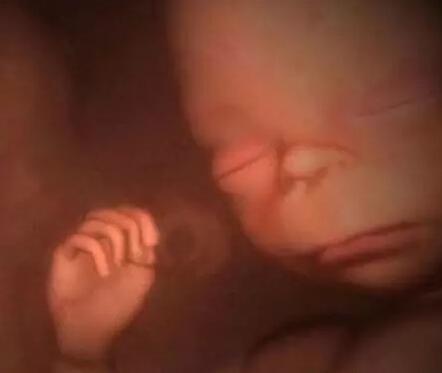

从4-D扫描图的特写镜头可以看到,这个差不多足月的胎儿在吸食羊水。这有助于胎儿为迎接子宫外的生活锻炼消化系统。